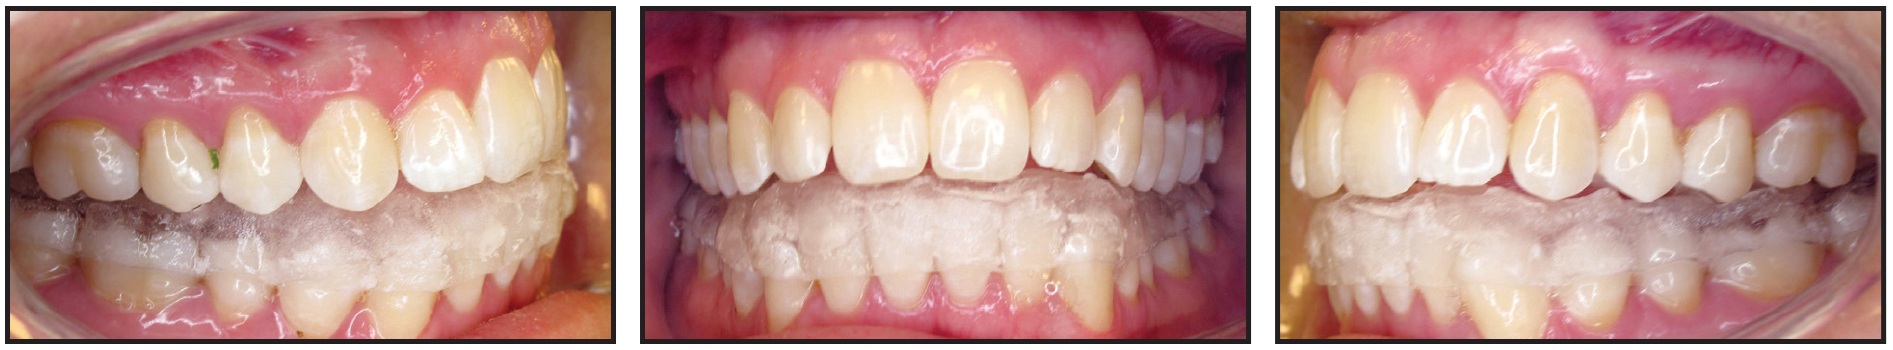

Eight weeks later, Class III sliding jigs were added, extending to the lower second molars, to provide direct distalization for Class III correction (Fig. 8). Elastics were worn from the upper first molars to anterior hooks on the sliding jigs.

Fig. 8 Class III sliding jigs extended to lower second molars to provide direct distalization for Class III correction; elastics attached from upper first molars to anterior hooks on sliding jigs.

After another nine weeks of treatment, the remaining teeth were bonded (Fig. 9). Vertical elastics were worn from the upper canines to the lower canines and first premolars. Finishing and detailing were carried out prior to debonding, and IPR was performed from lower canine to canine to resolve the Bolton discrepancy.

Fig. 9 Remaining teeth bonded nine weeks later.